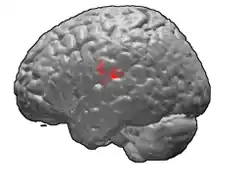

Brodmann area 43, the subcentral area, is a structurally distinct area of the cerebral cortex defined on the basis of cytoarchitecture. Along with Brodmann Area 1, 2, and 3, Brodmann area 43 is a subdivision of the postcentral region of the brain,[1] suggesting a somatosensory ('feeling of the body') function. The histological structure of Area 43 was initially described by Korbinian Brodmann, but it was not labeled on his map of cortical areas.[2]

In the human subcentral area 43, a sub area of the cytoarchitecture is defined in the postcentral region of the cerebral cortex. It occupies the postcentral gyrus, which is between the ventrolateral extreme of the central sulcus and the depth of the lateral sulcus, at the insula. Its rostral and caudal borders are approximated by the anterior subcentral sulcus and the posterior subcentral sulcus, respectively. Cytoarchitecturally, it is bounded rostrally, by the agranular frontal area 6, and caudally, for the most part, by the caudal postcentral area 2 and the supramarginal area 40.[1]